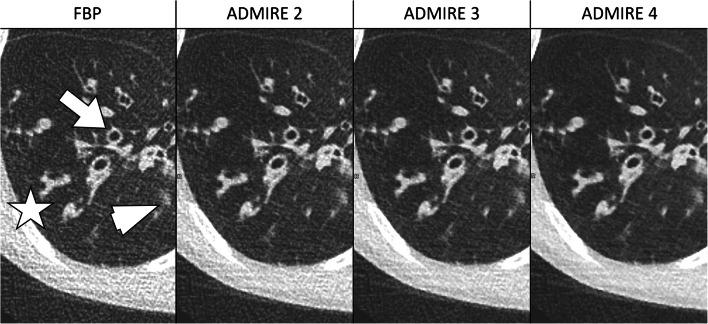

To assess the potential for maximum dose reduction of pediatric lung dual-source CT with spectral shaping and advanced iterative reconstruction (ADMIRE).

We retrospectively analyzed dual-source CT acquisitions in a full-dose group (FD: 100 kV, 64 reference mAs) and in three groups with spectral shaping and differing reference mAs values (Sn: 100 kV, 96/64/32 reference mAs), each group consisting of 16 patients (age mean 11.5 years, standard deviation 4.8 years, median 12.8 years, range 1.3-18 years). Advanced iterative reconstruction of images was performed with different strengths (FD: ADMIRE Level 2; Sn: ADMIRE Levels 2, 3 and 4). We analyzed dose parameters and measured noise. Diagnostic confidence and detectability of lung lesions as well as anatomical structures were assessed using a Likert scale (from 1 [unacceptable] to 4 [fully acceptable]).

Compared to full dose, effective dose was reduced to 16.7% in the Sn 96 group, 11.1% in Sn64, and 5.5% in Sn32 (P<0.001). Noise values of Sn64 did not statistically differ from those in FD (45.7 vs. 38.9 Hounsfield units [HU]; P=0.132), whereas noise was significantly higher in Sn32 compared to Sn64 (61.5 HU; P<0.001). A Likert score >3 was reached in Sn64 regarding diagnostic confidence (3.2) and detectability of lung lesions (3.3). For detectability of most anatomical structures, no significant differences were found between FD and Sn64 (P≥0.05).

In pediatric lung dual-source CT, spectral shaping together with ADMIRE 4 enable radiation dose reduction to about 10% of a full-dose protocol while maintaining an acceptable diagnostic quality.

评估使用光谱成形和高级迭代重建(ADMIRE)技术降低儿童肺部双源 CT 最大剂量的潜力。

我们回顾性分析了全剂量组(FD:100kV,64 参考 mAs)和三组光谱成形且参考 mAs 值不同的双源 CT 采集(Sn:100kV,96/64/32 参考 mAs),每组 16 例患者(年龄平均 11.5 岁,标准差 4.8 岁,中位数 12.8 岁,范围 1.3-18 岁)。使用不同强度的高级迭代重建图像(FD:ADMIRE Level 2;Sn:ADMIRE Levels 2、3 和 4)。我们分析了剂量参数并测量了噪声。使用李克特量表(1 表示不可接受,4 表示完全可接受)评估肺病变和解剖结构的诊断信心和可检测性。

与全剂量相比,Sn96 组有效剂量降低至 16.7%,Sn64 组降低至 11.1%,Sn32 组降低至 5.5%(P<0.001)。Sn64 的噪声值与 FD 相比无统计学差异(45.7 与 38.9 亨氏单位[HU];P=0.132),而 Sn32 的噪声值明显高于 Sn64(61.5 HU;P<0.001)。Sn64 在诊断信心(3.2)和肺病变可检测性(3.3)方面达到了>3 的李克特评分。对于大多数解剖结构的可检测性,FD 与 Sn64 之间无显著差异(P≥0.05)。

在儿童肺部双源 CT 中,光谱成形联合 ADMIRE 4 可使辐射剂量降低至全剂量方案的 10%左右,同时保持可接受的诊断质量。